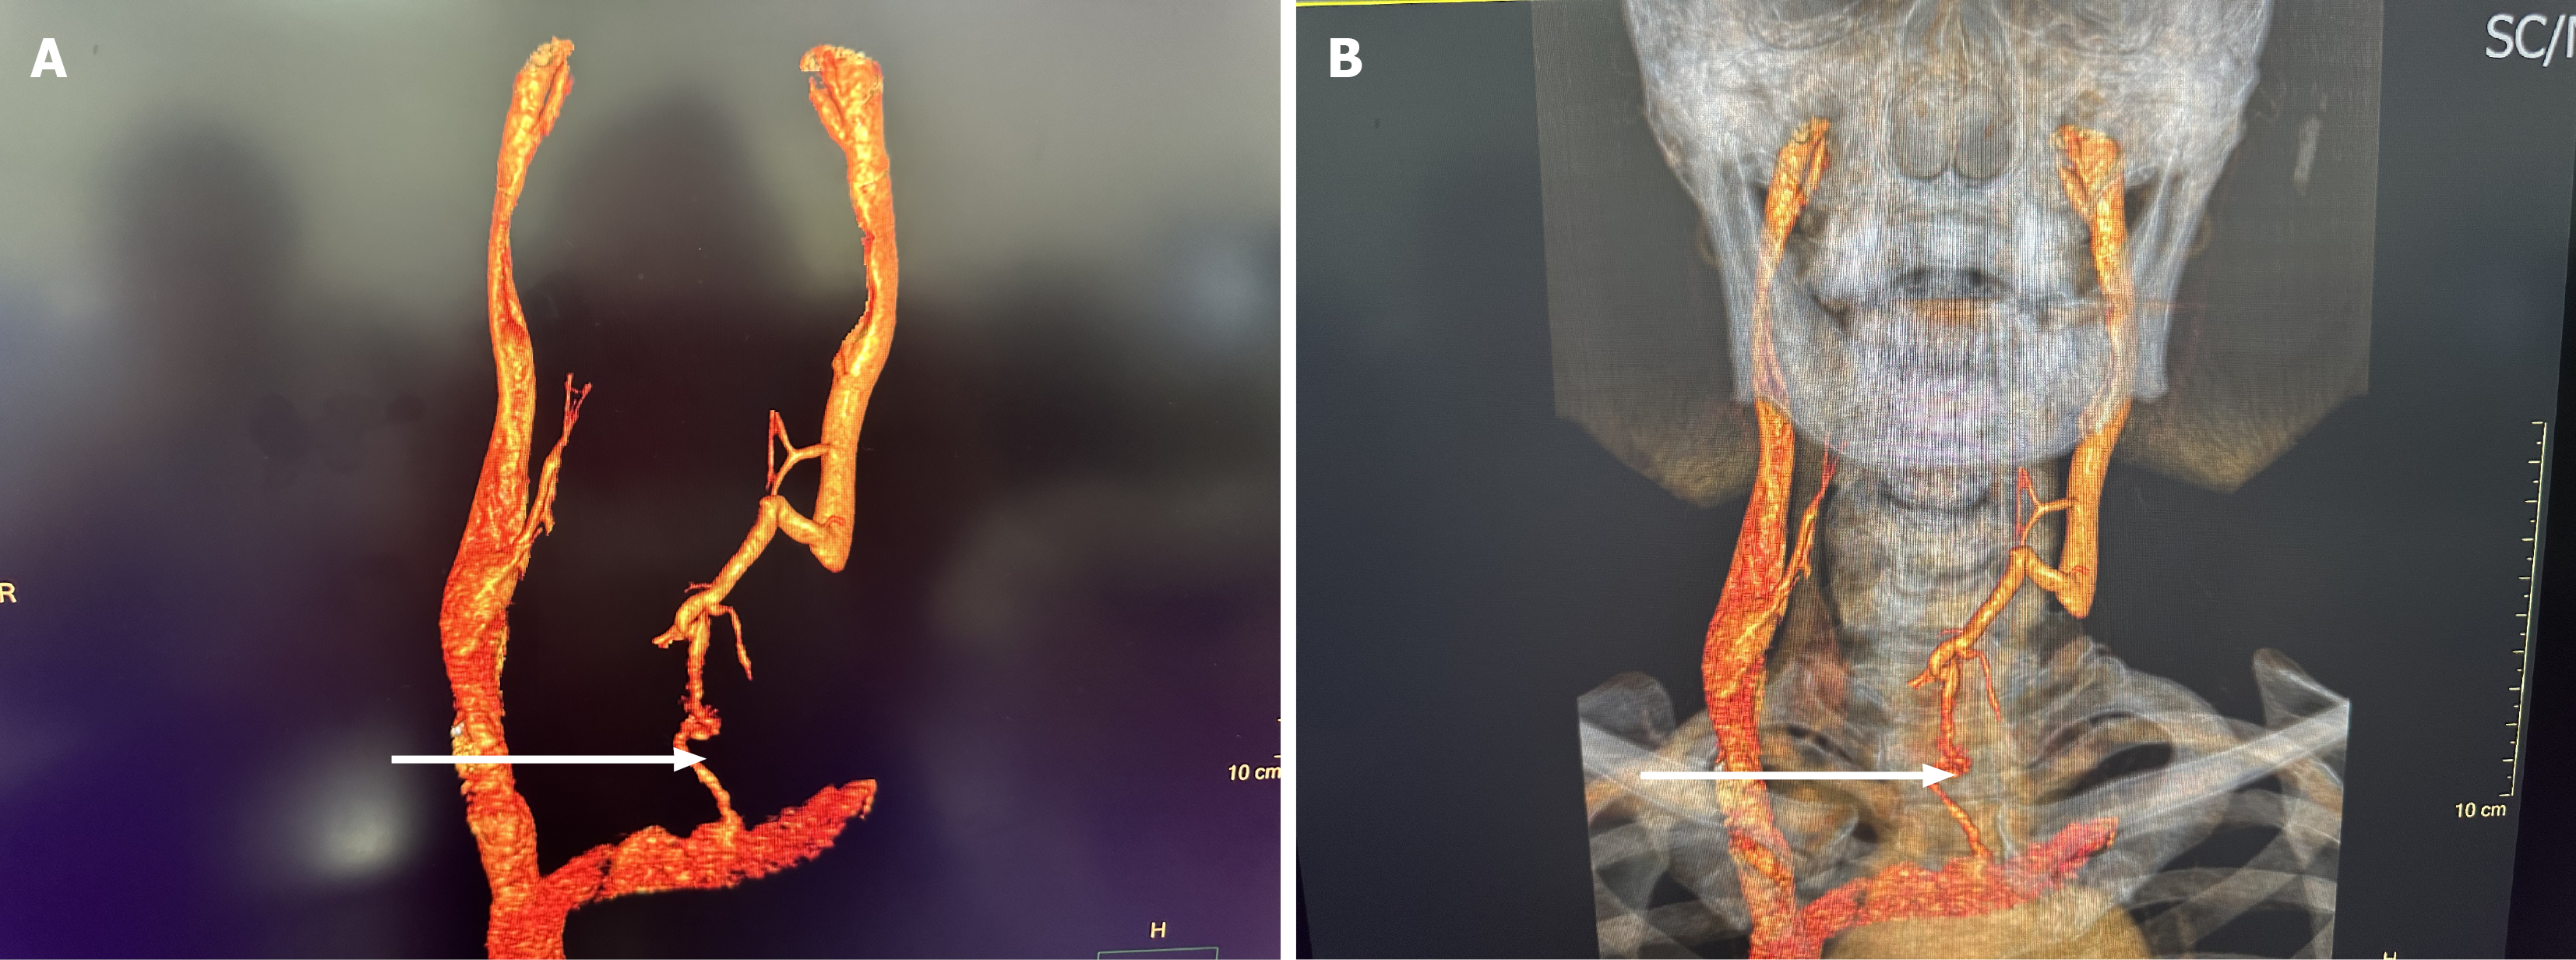

CT angiography/CT venography of head and neck vasculature: The lower portion of the left internal jugular vein was encased by the thyroid mass, with unclear visibility and local truncation. Collateral circulation was observed around the mass. The right internal jugular vein showed no abnormalities (Figure 3). A fiberoptic laryngoscopy revealed left vocal cord immobility, left vocal cord edema, and congestion with poor vocal cord closure.

Preoperative imaging modalities, including ultrasound, CT, and CT angiography (CTA)/CT venography (CTV), provided our team with comprehensive vascular invasion assessment, enabling meticulous preoperative planning. This evaluation allowed anticipation of potential vascular reconstruction requirements, even accounting for scenarios where vascular repair might prove technically unachievable. Concurrently, preoperative assessment indicated the common carotid artery was relatively intact, with full preservation anticipated; otherwise, artificial arterial anastomosis would be necessary. Corresponding contingency plans and preoperative consultations were established accordingly. Dikici et al[8] thinks that invasion of IJV (internal jugular vein) with hypervascular tumor thrombosis is an extremely rare condition in PTC. Thrombosis of IJV is probably underdiagnosed. Early-stage diagnosis is important for long-term survival rates.

Conducted meticulous preoperative assessments including: Thyroid function evaluation (TSH, free T4, thyroglobulin levels); cardiopulmonary function testing (echocardiography, pulmonary function tests); Laryngeal examination with preoperative vocal cord mobility assessment via flexible laryngoscopy; Contrast-enhanced CT angiography with 3D vascular reconstruction for anatomical localization; Postoperative Rehabilitation Program.